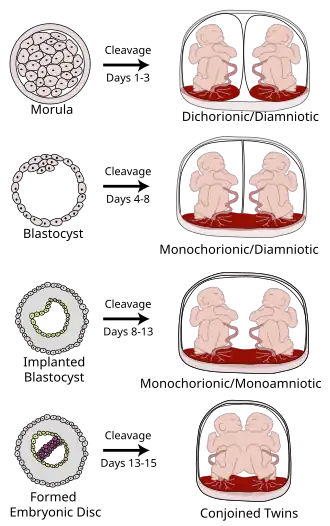

The degree of separation of the twins in utero depends on if and when they split into two zygotes. Dizygotic twins were always two zygotes. Monozygotic twins split into two zygotes at some time very early in the pregnancy. The timing of this separation determines the chorionicity (the number of placentae) and amniocity (the number of sacs) of the pregnancy. Dichorionic twins either never divided (i.e.: were dizygotic) or they divided within the first 4 days. Monoamnionic twins divide after the first week.

In very rare cases, twins become conjoined twins. Non-conjoined monozygotic twins form up to day 14 of embryonic development, but when twinning occurs after 14 days, the twins will likely be conjoined.[45] Furthermore, there can be various degrees of shared environment of twins in the womb, potentially leading to pregnancy complications.

It is a common misconception that two placentas automatically implies dizygotic twins, but if monozygotic twins separate early enough, the arrangement of sacs and placentas in utero is in fact indistinguishable from that of dizygotic twins.

| Type | Description | Day |

|---|---|---|

| Dichorionic–Diamniotic | Normally, twins have two separate (di- being a numerical prefix for two) chorions and amniotic sacs, termed Dichorionic–Diamniotic or "DiDi". It occurs in almost all cases of dizygotic twins (except in very rare cases of fusion between their blastocysts[46]) and in 18–36%[47] (or around 25%[46]) of monozygotic (identical) twins.

DiDi twins have the lowest mortality risk at about 9 percent, although that is still significantly higher than that of singletons.[48] |

Dichorionic-Diamniotic twins form when splitting takes place by the third day after fertilisation.[46] |

| Monochorionic–Diamniotic | Monochorionic twins share the same placenta.

Monochorionic twins generally have two amniotic sacs (called Monochorionic–Diamniotic "MoDi"), which occurs in 60–70% of the pregnancies with monozygotic twins,[47] and in 0.3% of all pregnancies.[49] Monochorionic-Diamniotic twins are almost always monozygotic, with a few exceptions where the blastocysts have fused.[46] Monochorionic twins share the same placenta, and thus have a risk of twin-to-twin transfusion syndrome. |

Days 4–8 |

| Monochorionic–Monoamniotic | Monochorionic twins share the same amnion in 1–2% of monozygotic twin pregnancies.[47]

Monoamniotic twins are always monozygotic.[50] The survival rate for monoamniotic twins is somewhere between 50%[50] and 60%.[51] Monoamniotic twins, as with diamniotic monochorionic twins, have a risk of twin-to-twin transfusion syndrome. Also, the two umbilical cords have an increased chance of being tangled around the babies. Because of this, there is an increased chance that the newborns may be miscarried or suffer from cerebral palsy due to lack of oxygen. |

Monoamniotic twins occur when the split takes place after the ninth day after fertilization.[46] |

| Conjoined twins |

When the division of the developing zygote into 2 embryos occurs, 99% of the time it is within 8 days of fertilization. Mortality is highest for conjoined twins due to the many complications resulting from shared organs. |

If the division of the zygote occurs later than the 12 days then conjoined twins are usually the result. |

Conjoined twins

Conjoined twins (or the once-commonly used term "siamese") are monozygotic twins whose bodies are joined during pregnancy. This occurs when the zygote starts to split after day 12[46] following fertilization and fails to separate completely. This condition occurs in about 1 in 50,000 human pregnancies. Most conjoined twins are now evaluated for surgery to attempt to separate them into separate functional bodies. The degree of difficulty rises if a vital organ or structure is shared between twins, such as the brain, heart, liver or lungs.